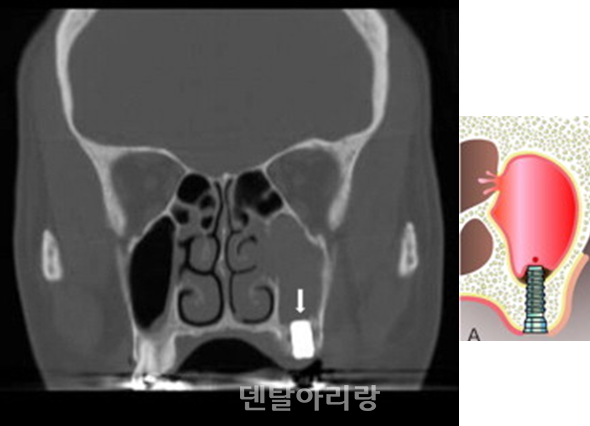

해부학적으로 상악동 외측벽 골내 동맥은 치조정(alveolar crest)으로부터 평균 약 16mm±3.5mm 상방에서 주행한다고 알려져 있으므로 골창의 상방 골삭제 선이 이 부위보다 하방에 위치하도록 디자인을 설정해야 한다. 상악동 골이식을 위한치조정 접근법은 상대적으로 측벽 접근 방법에 비해 상대적으로 출혈 등 합병증 발생이 적다고 할 수 있으나, 전혀 예기치 못하게 출혈이 간혹 발생하므로 주의가 필요하다. 치조종 접근법 후, 발생하는 출혈은 대부분 상악동 아래 바닥을 주행하는 상악 후상치조 동맥(posterior superior alveolar artery)의 손상과 관련이 있다<그림 13>.

△그림 13. 치조정 접근법에 의한 임플란트 식립 후, 상악동내 출혈

이런 경우, 구강 내로는 출혈이 없이 상악동과 상악동을 통해 비강으로 연결되는 매우 심각한 비출혈이 일어나며, 지혈이 어렵기 때문에 대부분 응급 상황으로 이어지게 된다. 따라서, 치조정 접근법을 통해 임플란트 식립 후, 구강내 출혈이 없더라도 환자가 수술 직후, 또는 귀가 후에 다량의 비출혈 증상을 호소하면 응급실을 통한 구강악안면외과 전문의에게 즉시 의뢰하여야 한다.